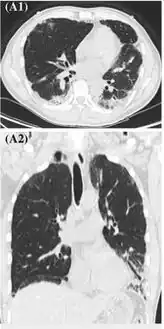

| CT scan of the chest showing diffuse lung infiltrates found in three cases of vaping-associated pulmonary injury | |

There are non-specific laboratory abnormalities that have been reported in association with the disease, including elevations in white blood cell count (with neutrophilic predominance and absence of eosinophilia), transaminases, procalcitonin, and inflammatory markers.[4][59] Infectious disease testing, including blood and sputum cultures and tests for influenza, Mycoplasma, and Legionella were all found to be negative in the majority of reported cases.[59] Imaging abnormalities are typically bilateral and are usually described as "pulmonary infiltrates or opacities" on chest X-ray and "ground-glass opacities" on chest CT.[4]

High-resolution computed tomography reveals patchy consolidation, ground-glass opacification in bilateral lower lungs